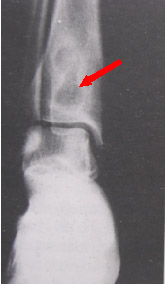

局限性骨膿腫患者表現為局部隱痛、腫、熱,有時毫無不適。一旦體質差,可局部急性發作。X片示乾骺端囊樣破壞區,周圍骨質硬化,直徑1~7cm不等,有時在病灶內可能有小死骨碎片。經抗生素治療和休息可好轉,但不能根治,易復發。

局限性骨膿腫1、X線檢查:表現為長骨幹骺端有橢圓形密度減低區,邊緣有清晰的骨質硬化,病變與鄰近正常骨髓腔境界清楚。需與骨囊腫鑑別。骨囊腫周圍只有薄層成帶狀硬化骨。

X線片表現為骨端有局限性密度減低區,其周圍骨質有炎性反應性增高陰影,且與周圍骨質分界不清一般多無骨膜反應及死骨。此種狀態應與骨囊腫鑑別後者主要顯示為囊腔周圍只有薄層帶狀硬化骨。